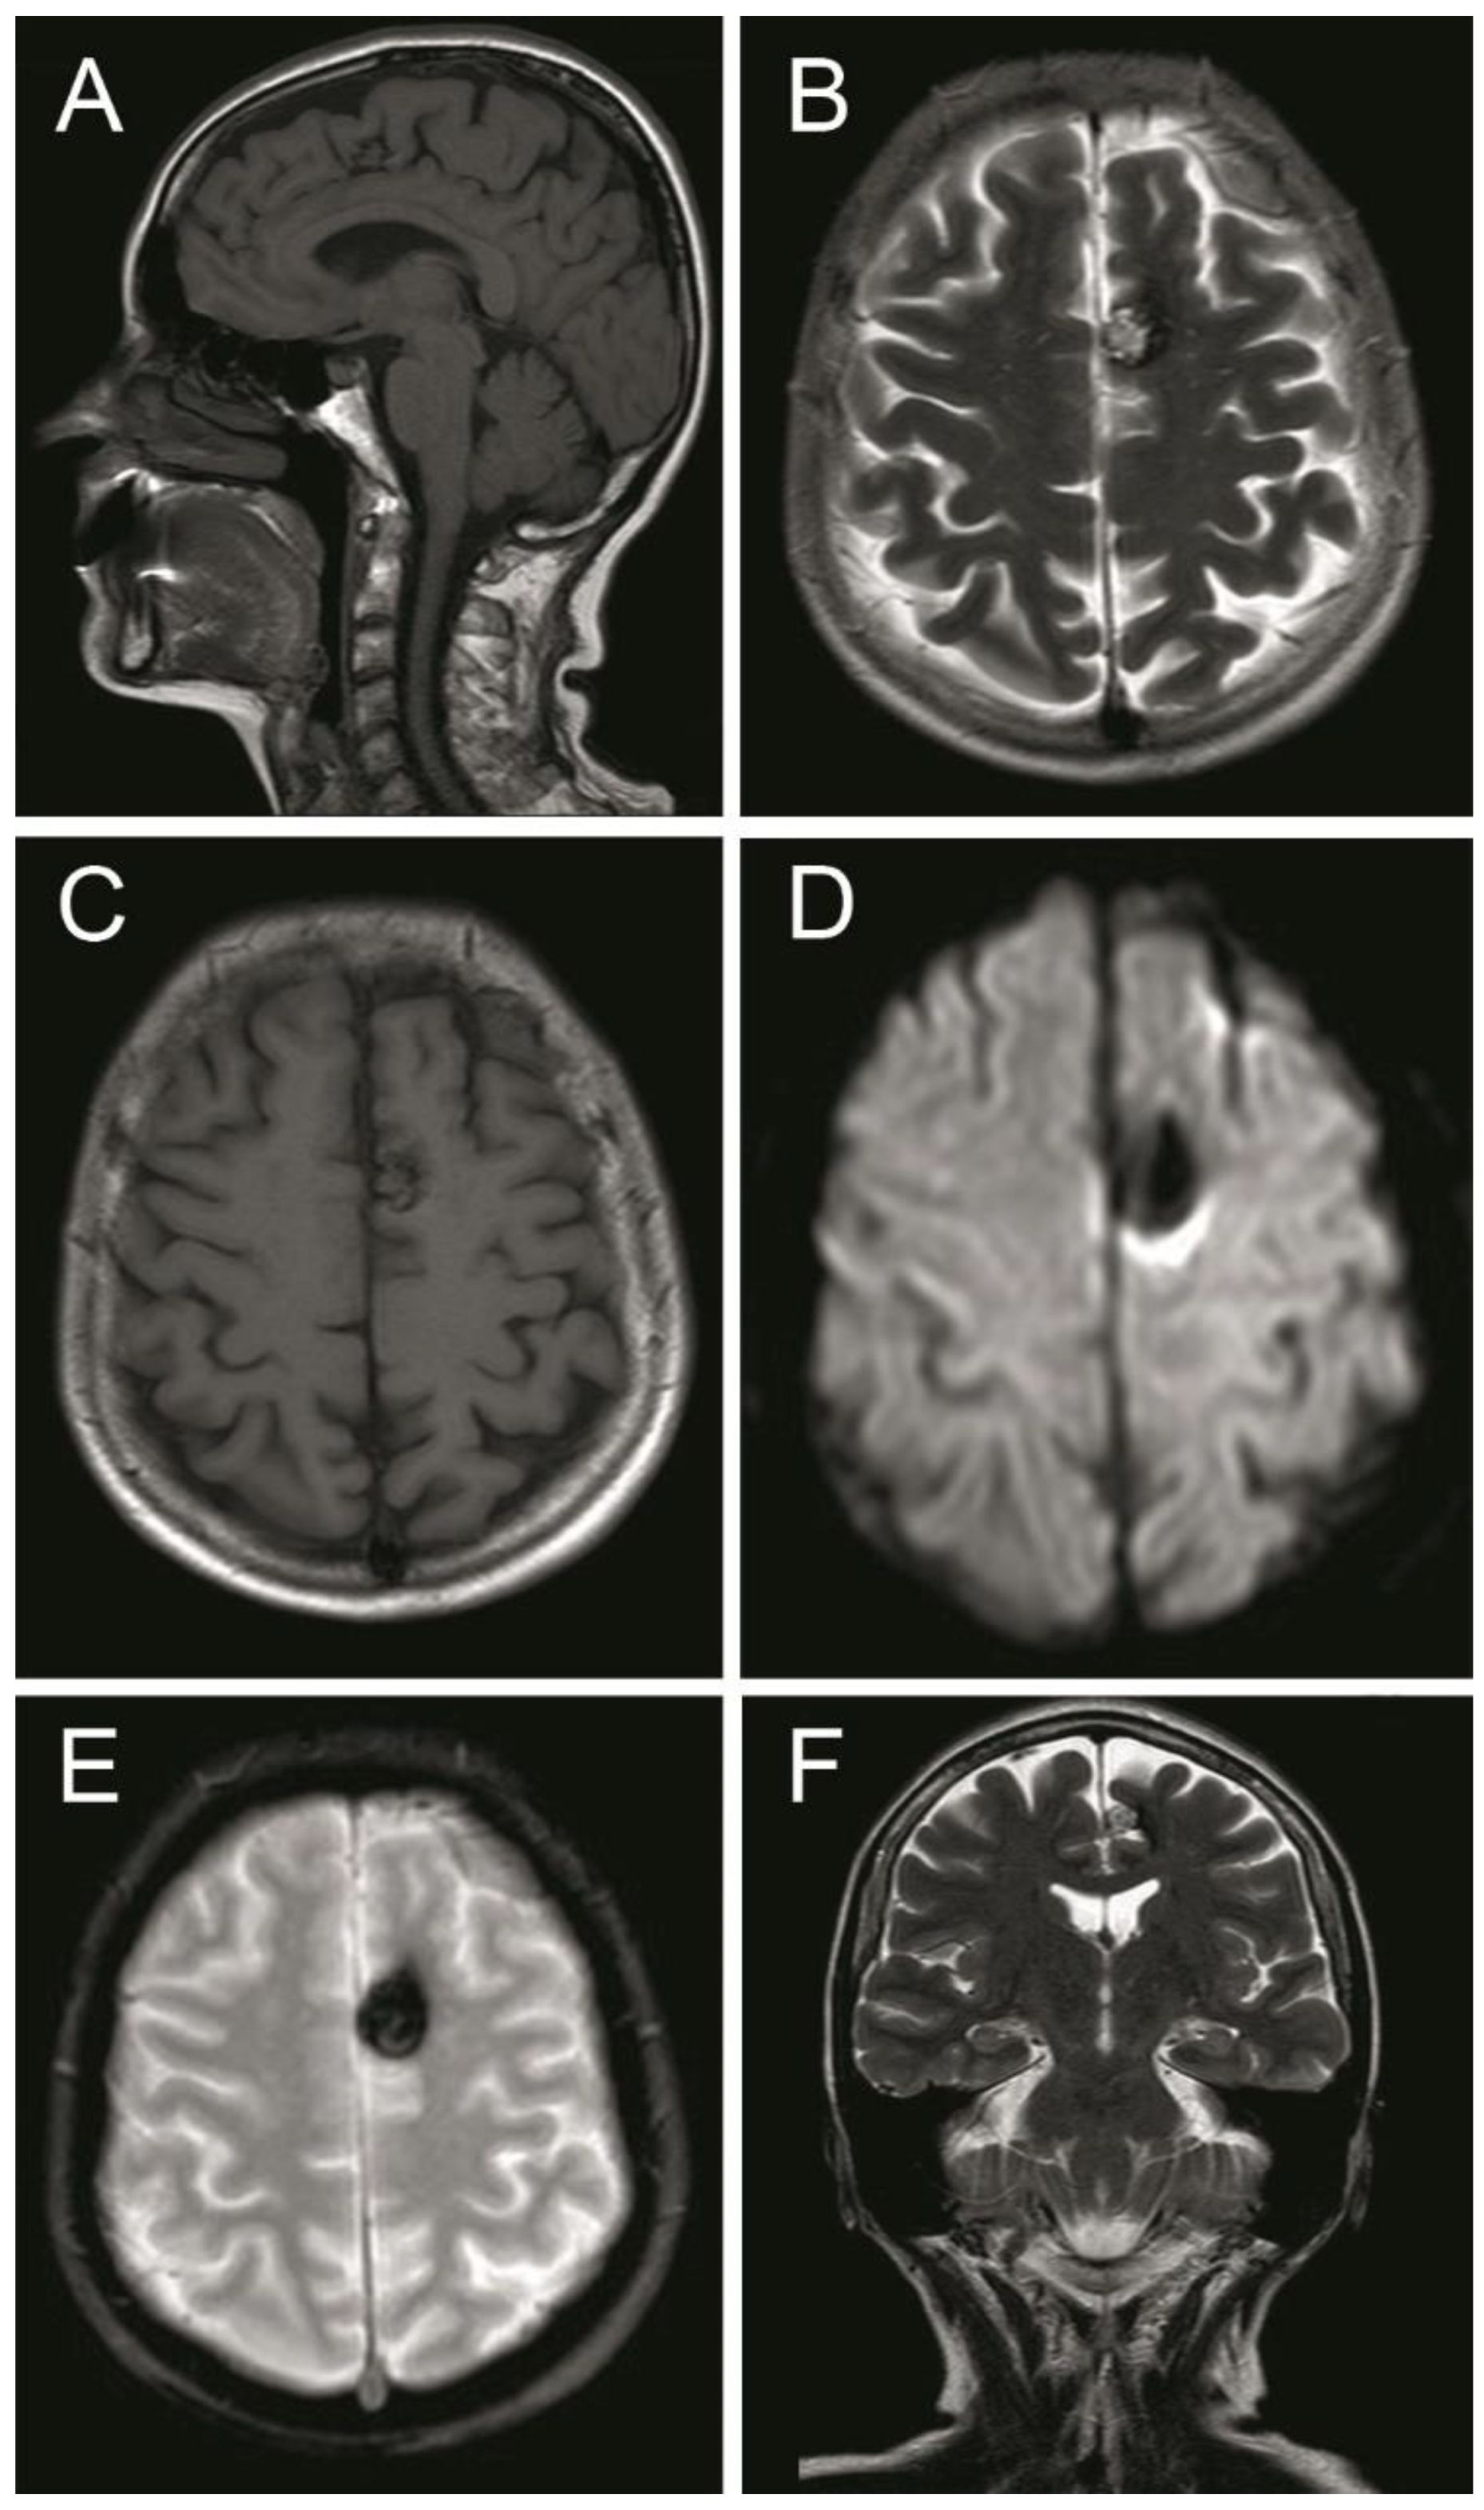

2. Case Presentation